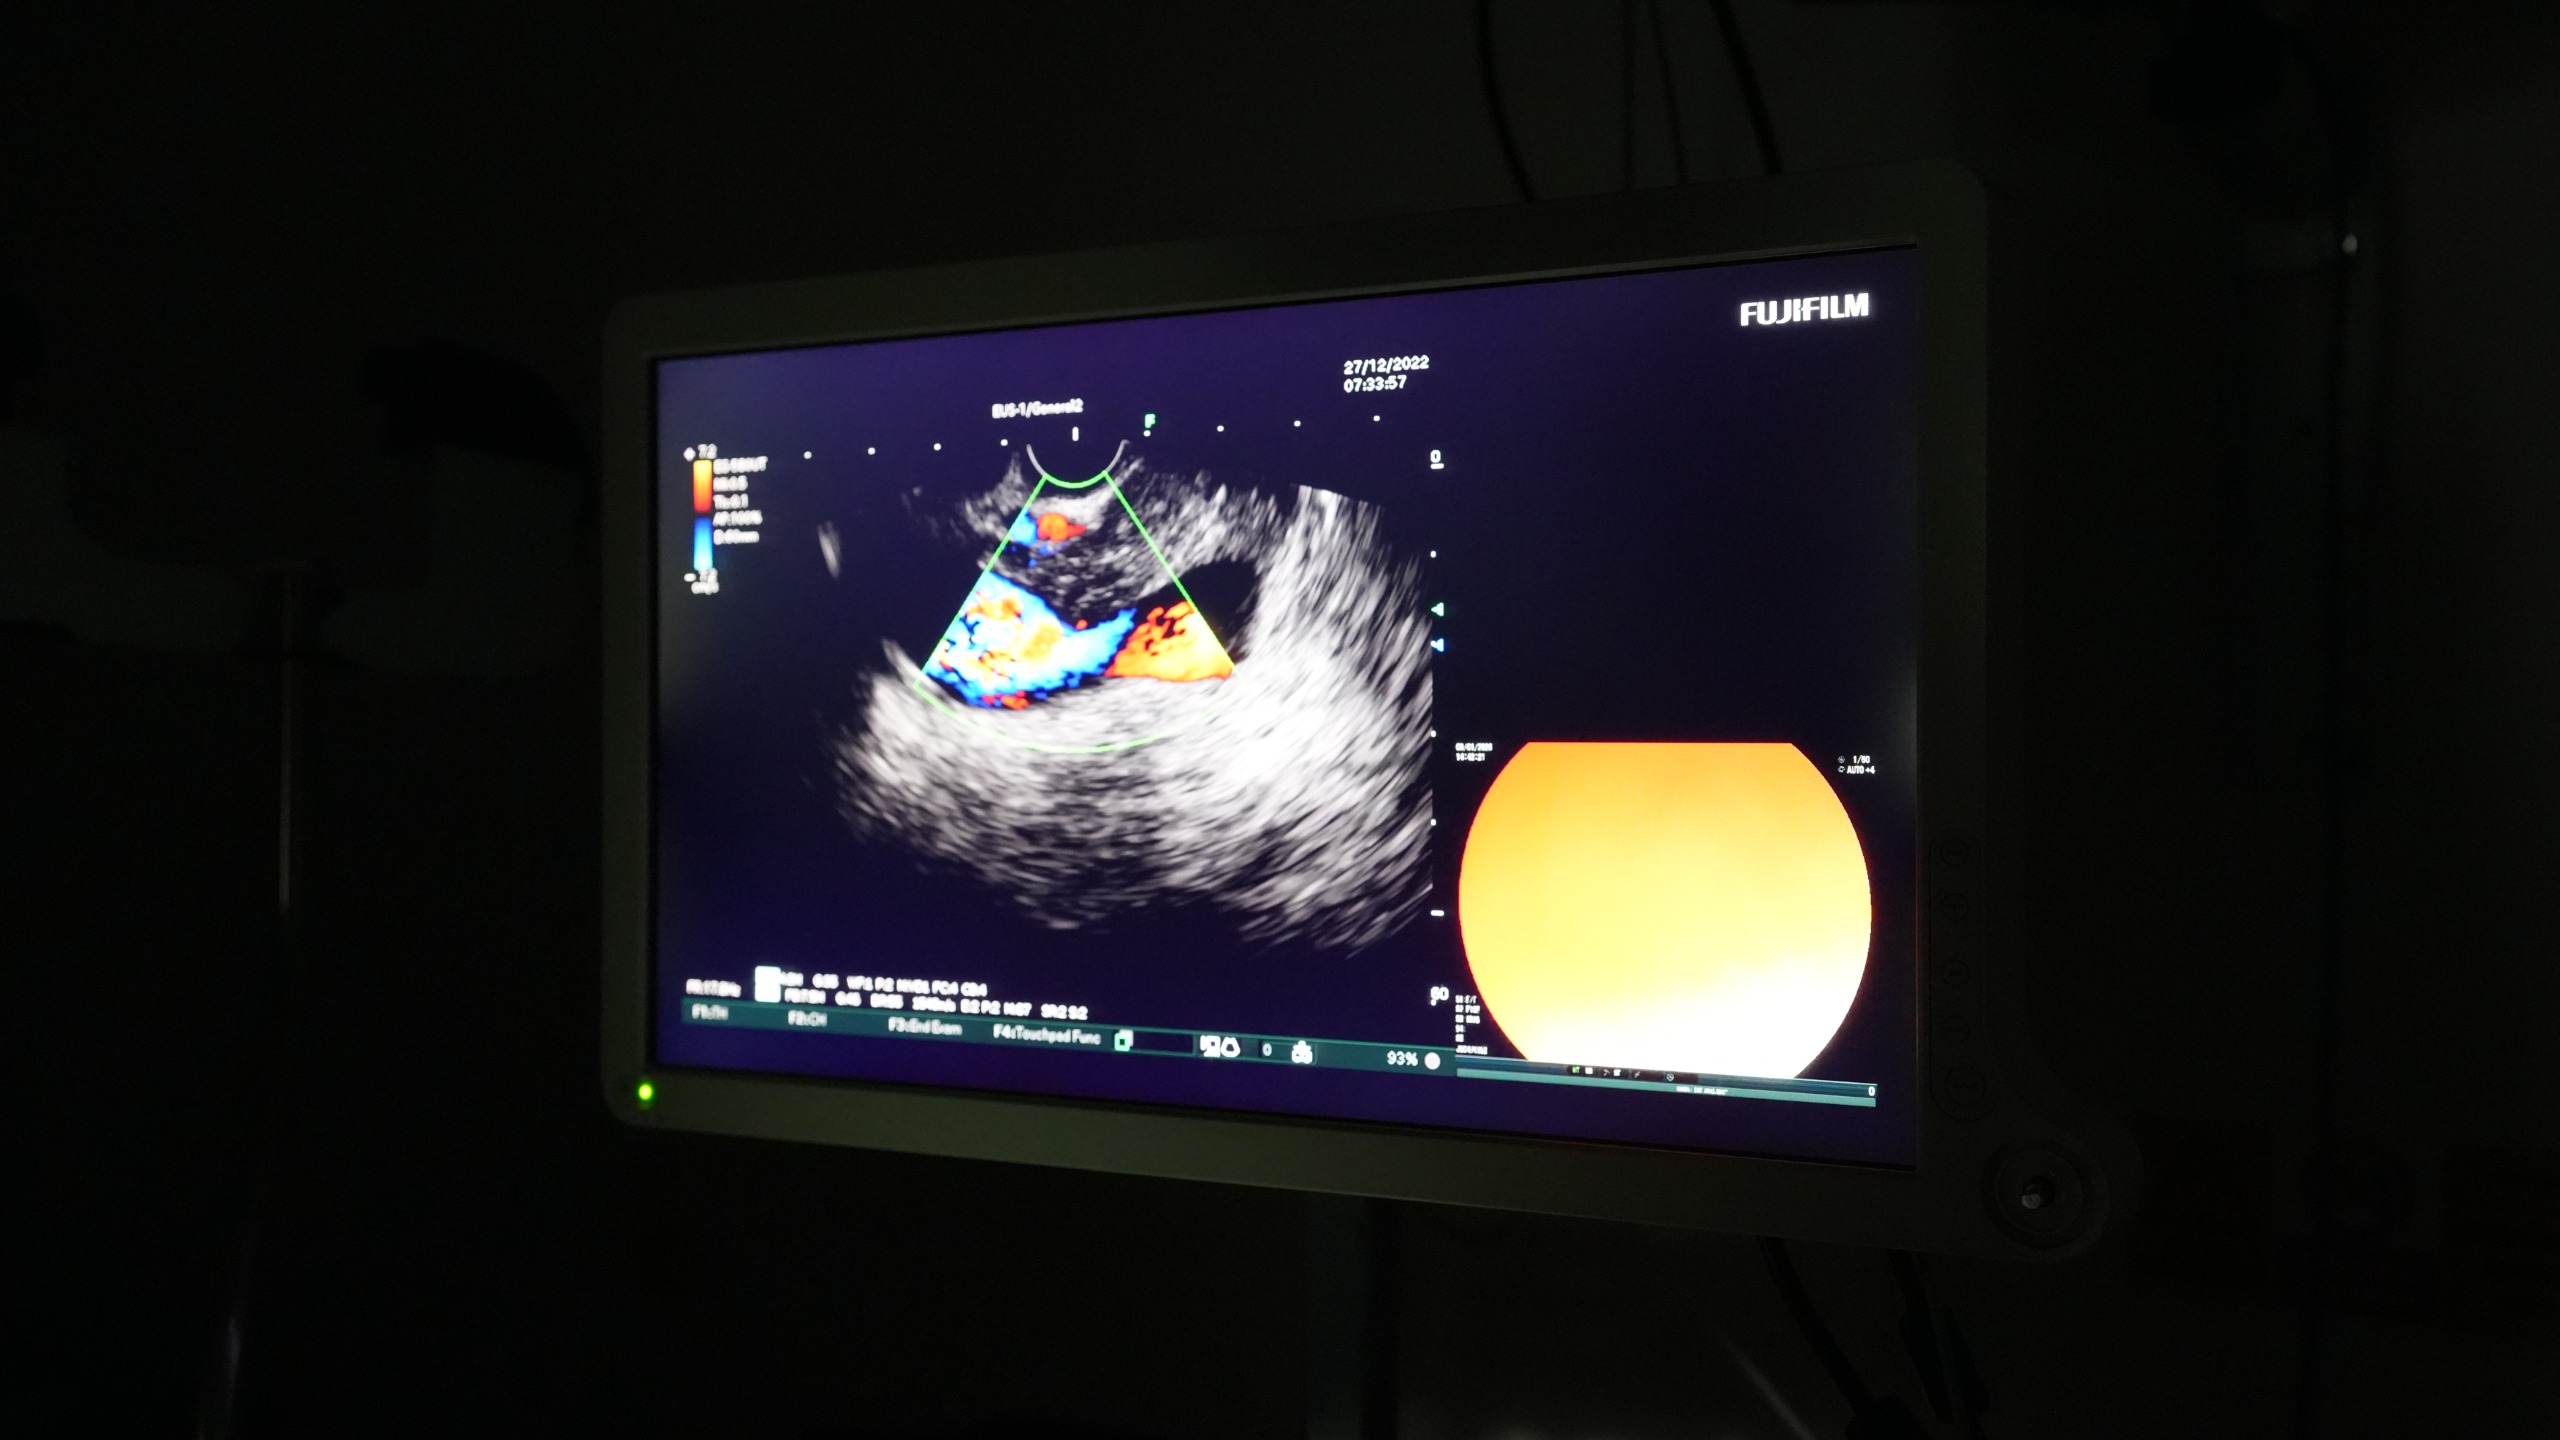

EUS yöntemiyle; özofagus submukozal lezyonları, mide submukozal lezyonları, pankreas lezyonları (kitle ve kistler) ile koledok lezyonlarının tanısı yapılabiliyor. Bu yöntem sayesinde sindirim sistemi ve çevresindeki organlara ait hastalıkların daha ayrıntılı ve doğru şekilde değerlendirilmesi mümkün oluyor.

“Endoskopik Ultrasonografi; özellikle pankreas ve sindirim sistemi kaynaklı hastalıkların tanısında son derece önemli bir yöntemdir. EUS sayesinde lezyonlar detaylı şekilde değerlendirilebilmekte, gerekli durumlarda hedefe yönelik biyopsi alınabilmektedir.” dedi.